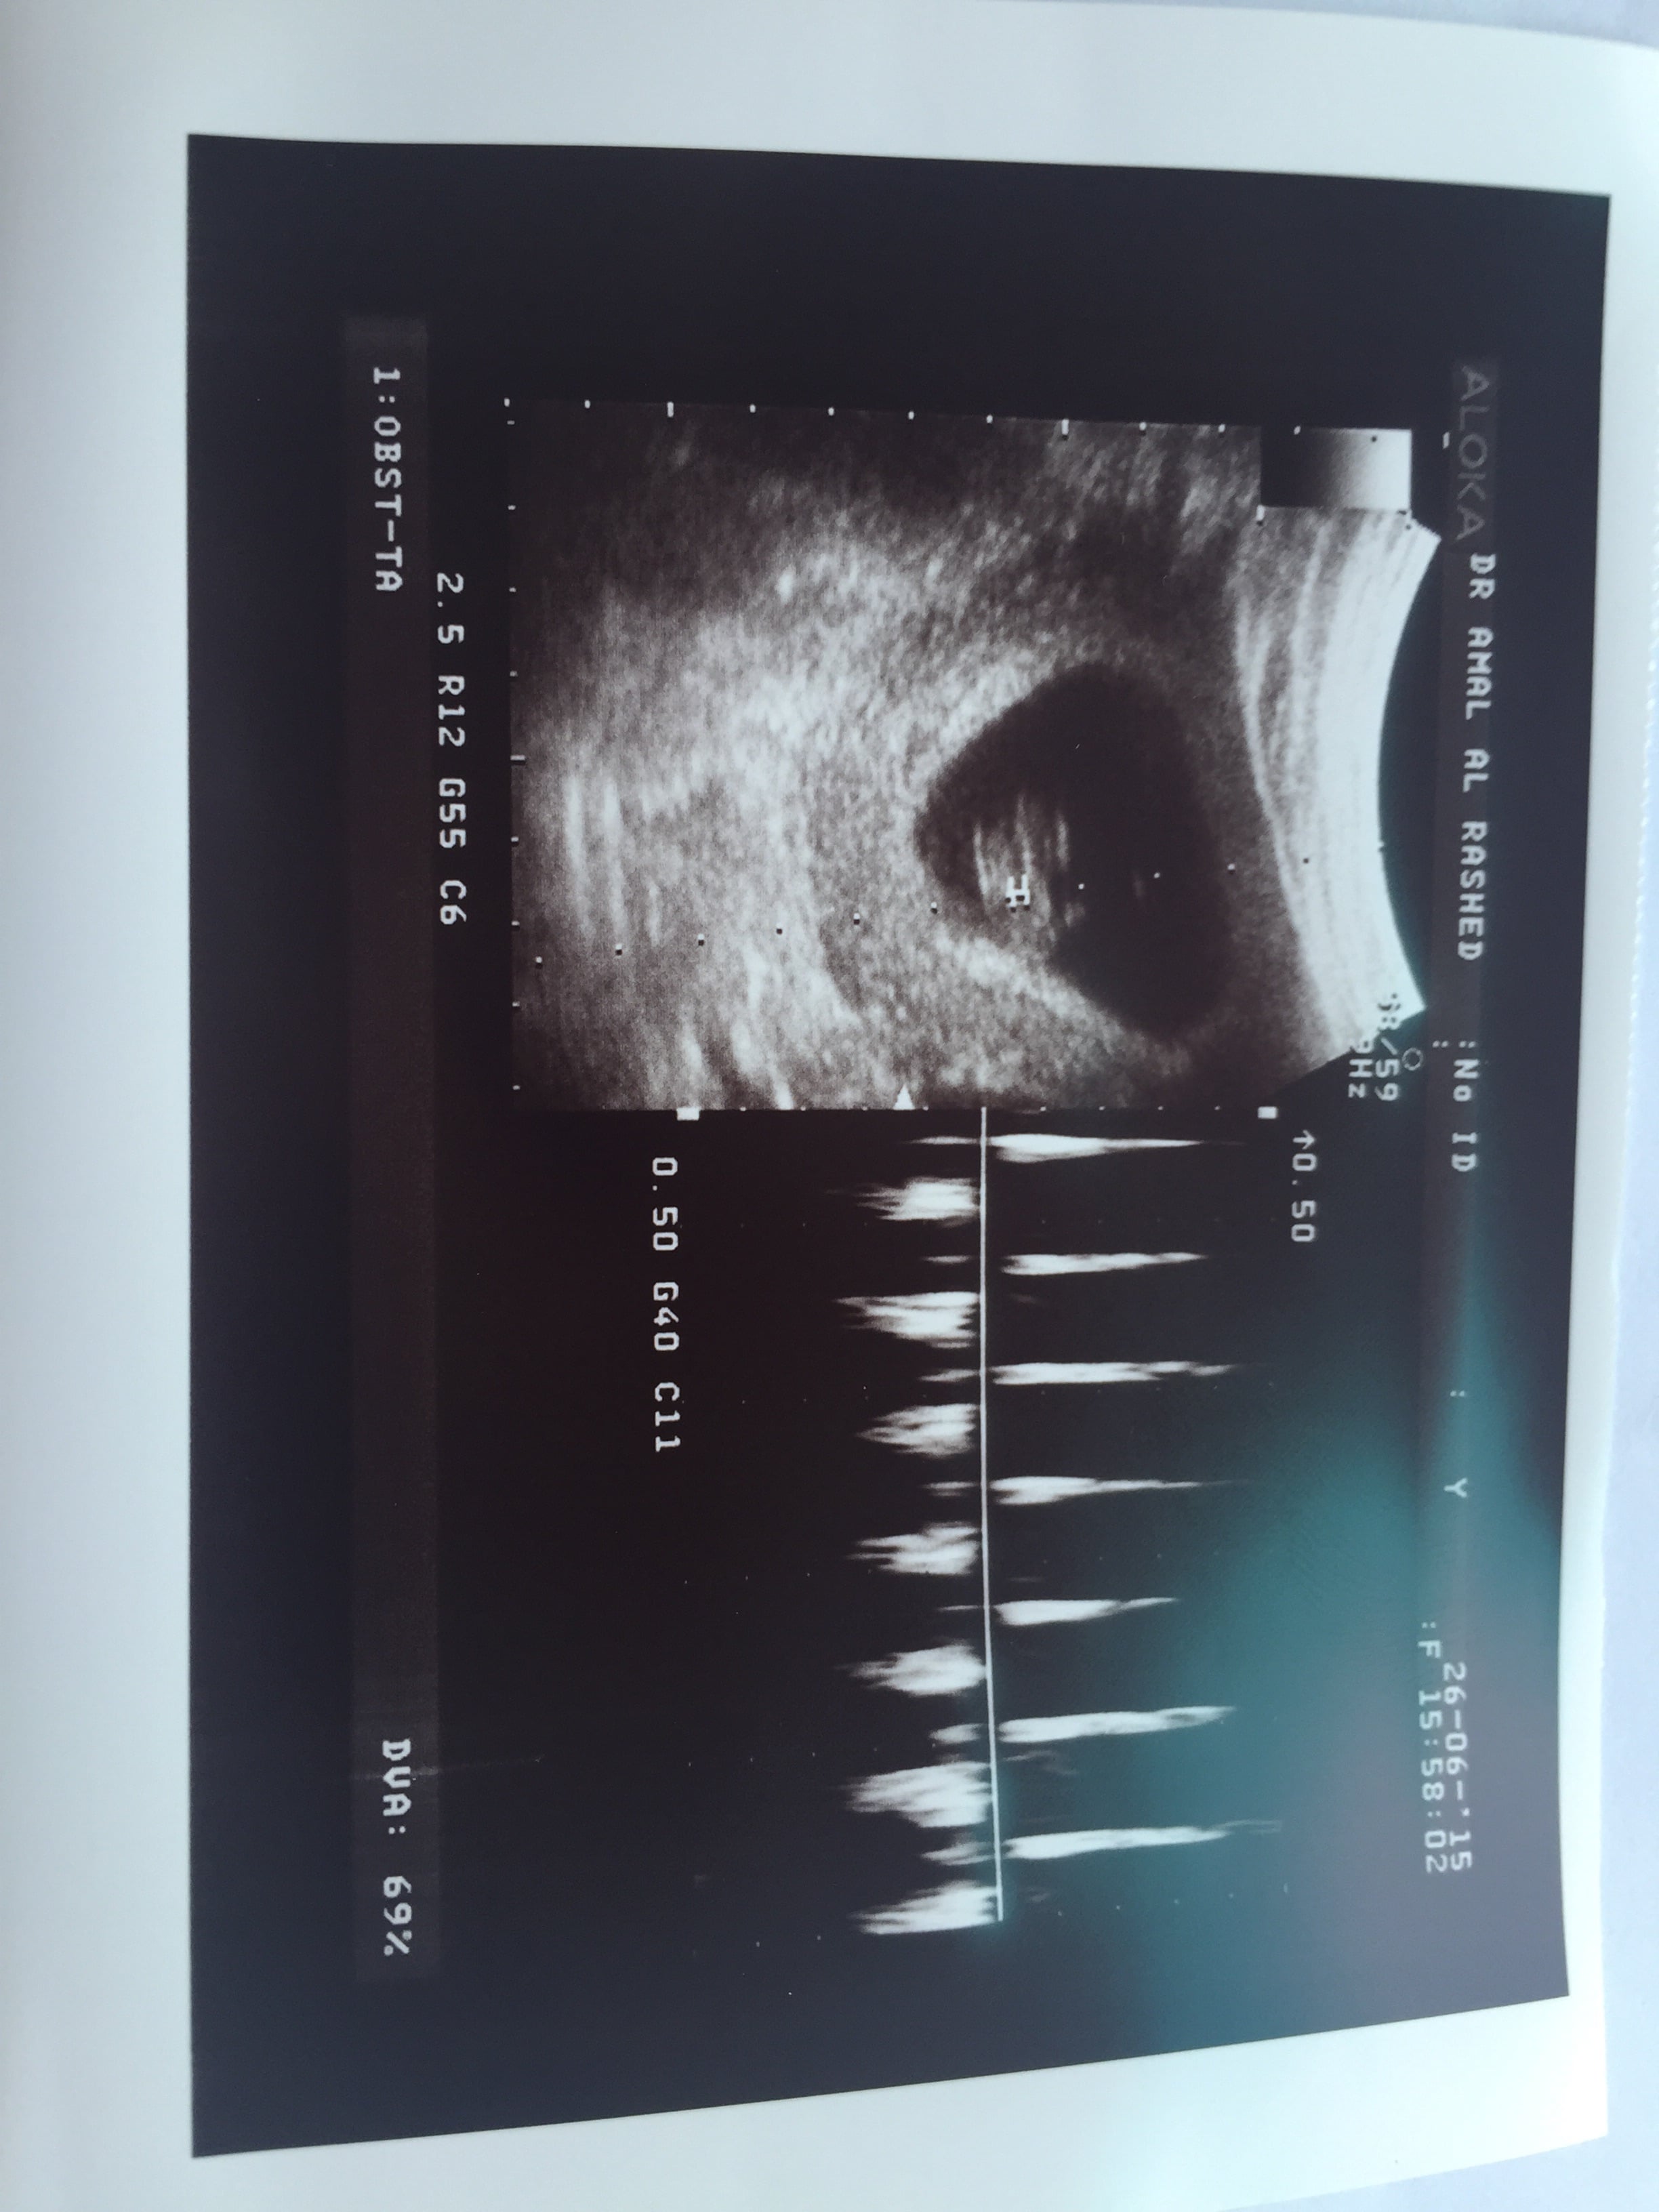

• Hi! Can someone help me with mine! 8w4d abdominal US